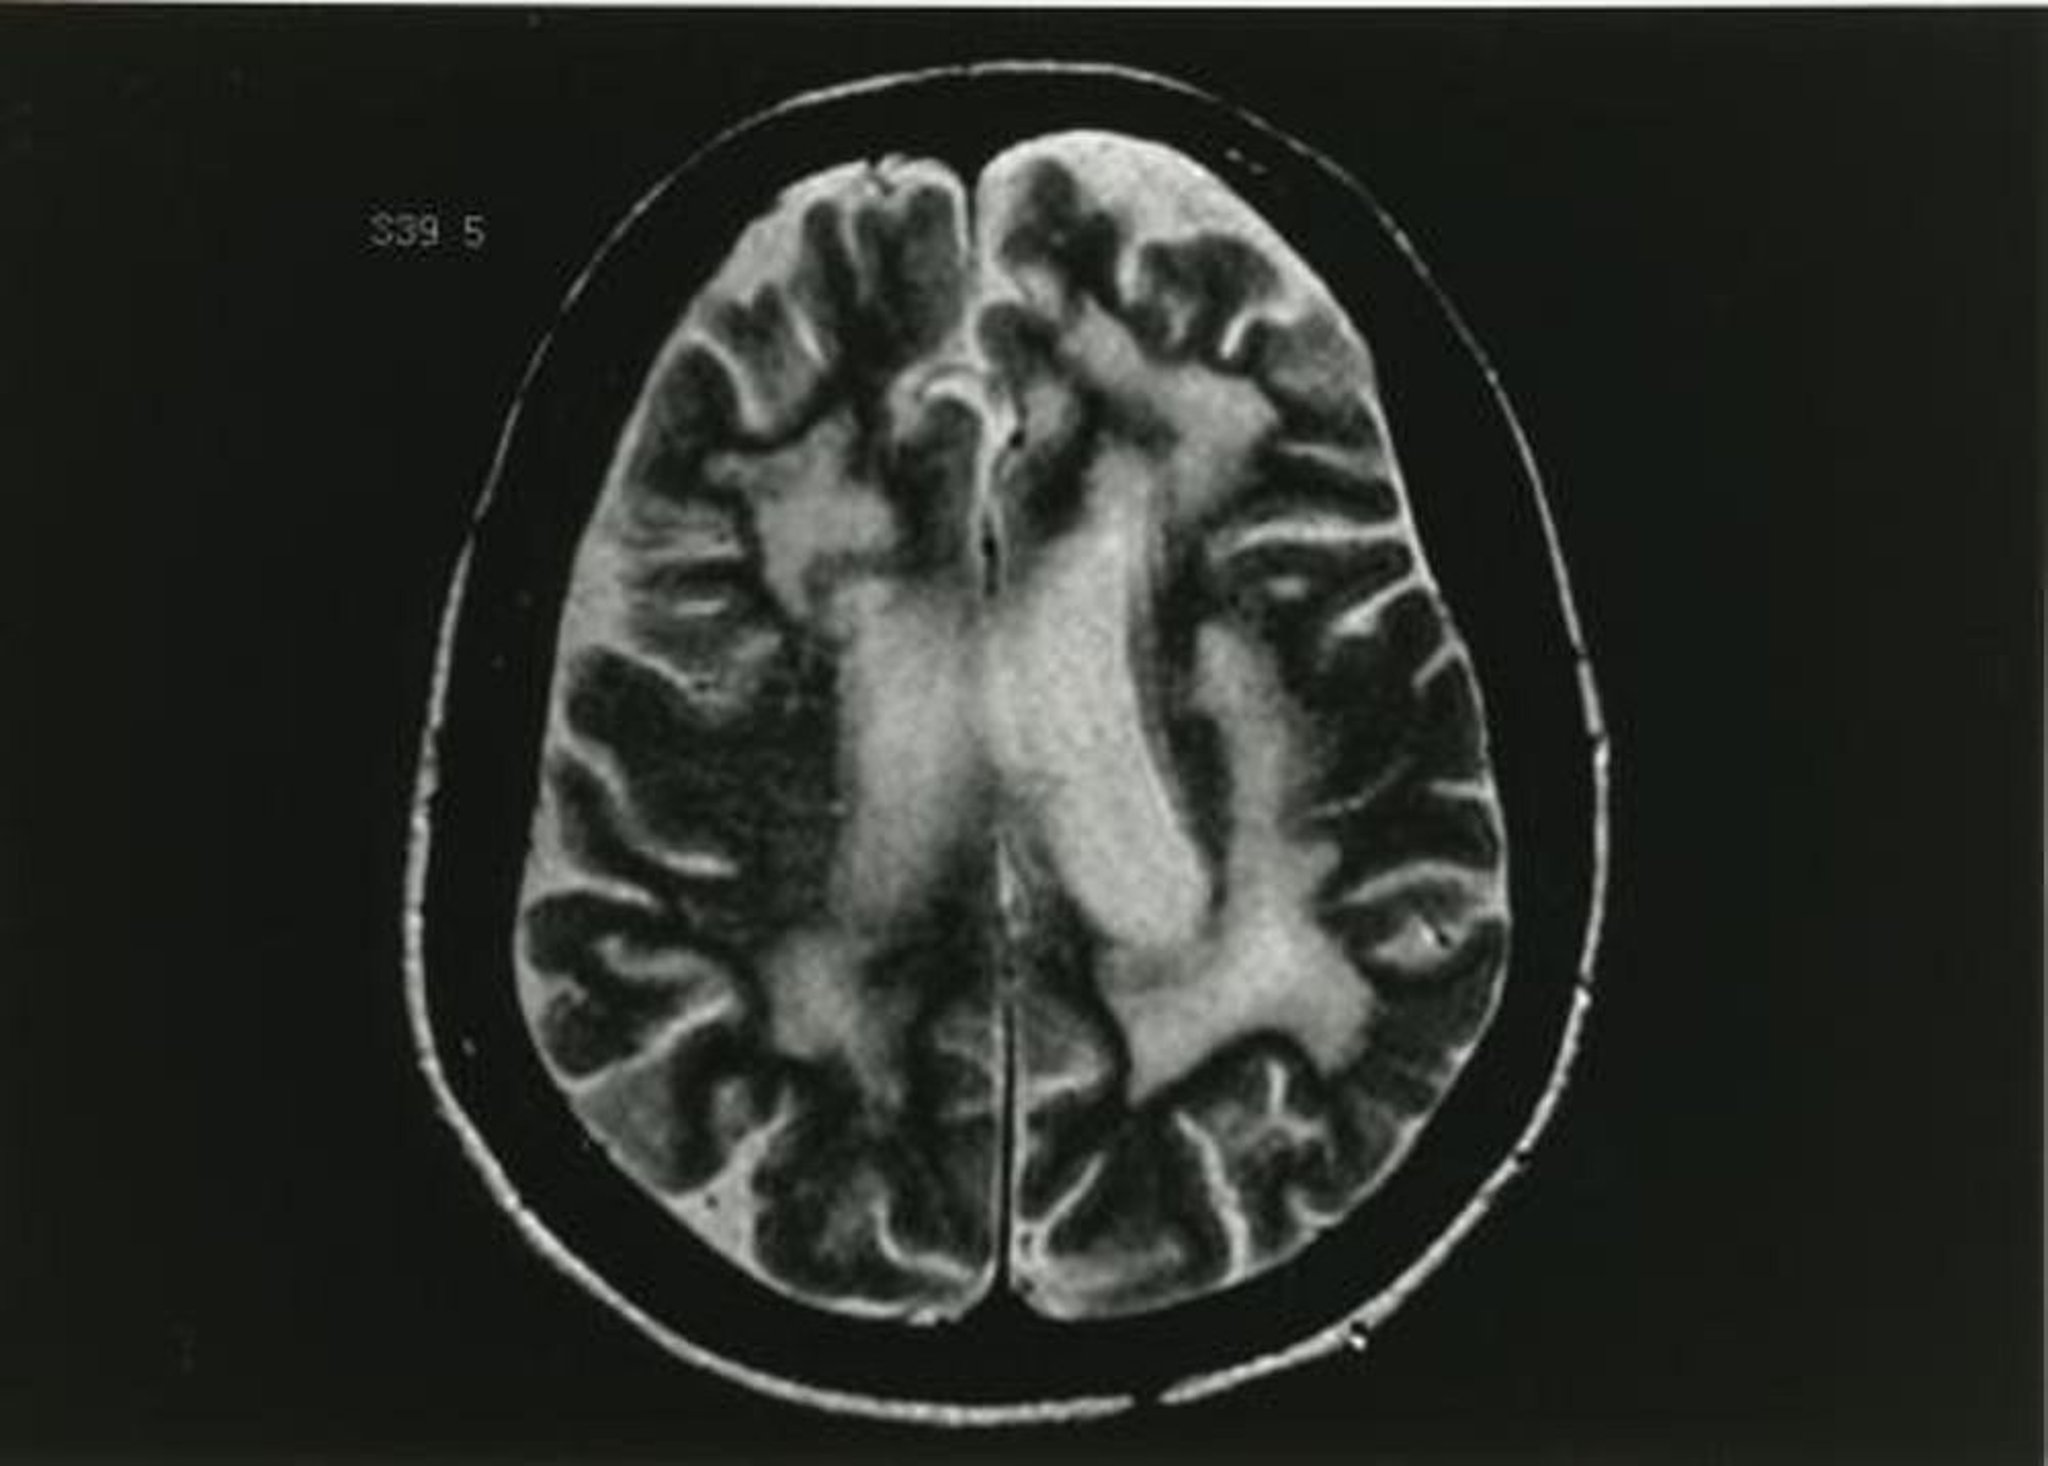

Esta imagen de RM ponderada en T2 muestra múltiples cambios en la sustancia blanca.

Imagen proporcionada por John E. Greenlee, MD.